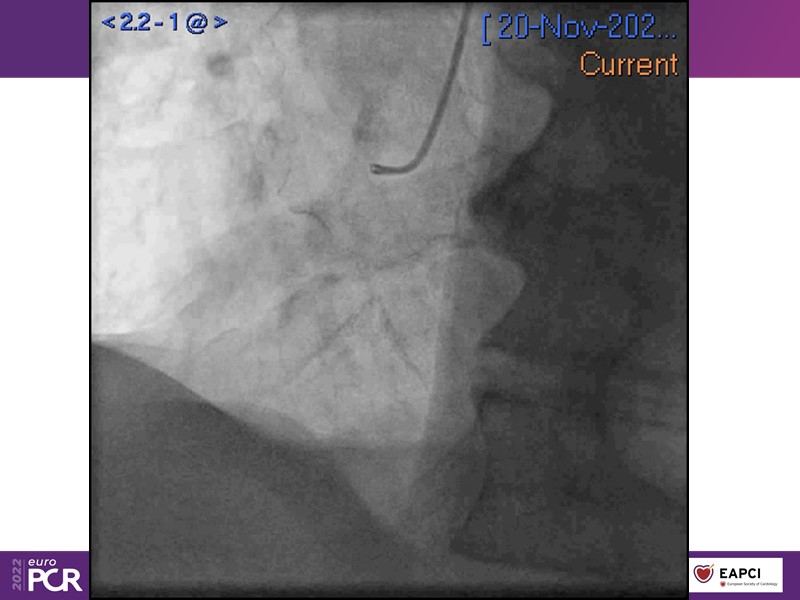

- To find out more about the application and mechanism of a sirolimus coated balloon for coronary artery disease treatment with case presentations in complex settings

- To understand how useful is a DES and DCB stent platform in complex coronary artery disease settings with case demonstrations and follow-up in diabetes mellitus